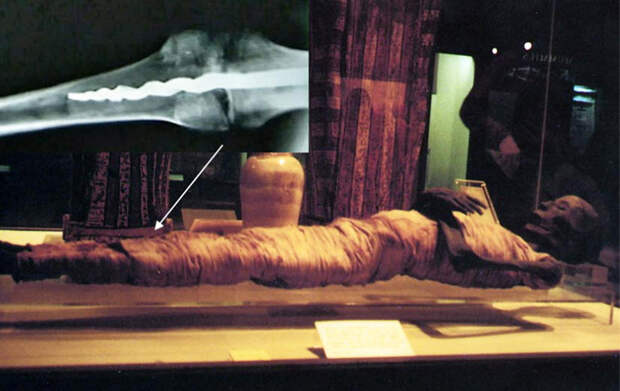

В 1971 году в музей Розенкрейца, расположенный в городе Сан-Хосе в Калифорнии, привезли запечатанный древнеегипетский гроб, внутри которого лежала хорошо сохранившаяся мумия, которая когда-то была телом очень знатного египтянина.

Когда в 70-х работники музея Розенкрейца получили запечатанный древнеегипетский гроб, они не знали, что внутри всё ещё лежала мумия. Ко всему прочему, исследования показали, что изначально саркофаг принадлежал другой мумии – по имени Юзермонту («мощь Монту») – а затем, спустя многие годы после его смерти, другую мумию положили в гроб Юзермонту. Тем не менее, новая мумия неизвестного происхождения стала известной под именем изначального хозяина саркофага. Анализ процедуры бальзамирования показал, что Юзермонту был мужчиной из верхушки древнеегипетского общества и жил во времена Нового царства (период между 16-11 вв. до Рождества Христова). Длина мумифицированного тела 1,5 м, присутствуют следы рыжих волос.

В августе 1995 профессор Уилфред Григгз из университета Бригама Янга, расположенного в штате Юта, вместе с группой экспертов просветил рентгеном шесть мумий, включая мумию Юзермонту, из музея Розенкрейца, расположенного в Сан-Хосе. Это было сделано перед тем, как он прочитал там лекцию. Специалисты были поражены, когда рентген показал, что в левое колено одной из мумий вставлен металлический штифт длиной 23 см.